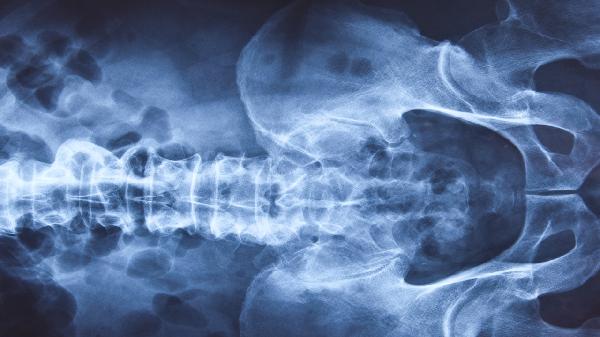

1、X线检查。

X线检查仍然是目前食管裂孔疝最重要的检查方法。但对于轻度食管裂孔疝,往往是反复的,一次检查没有问题,不能立即排除疾病。对于高度可疑的症状,应继续反复检查,取仰卧头等各种姿势,钡餐造影,最终得出诊断结论。